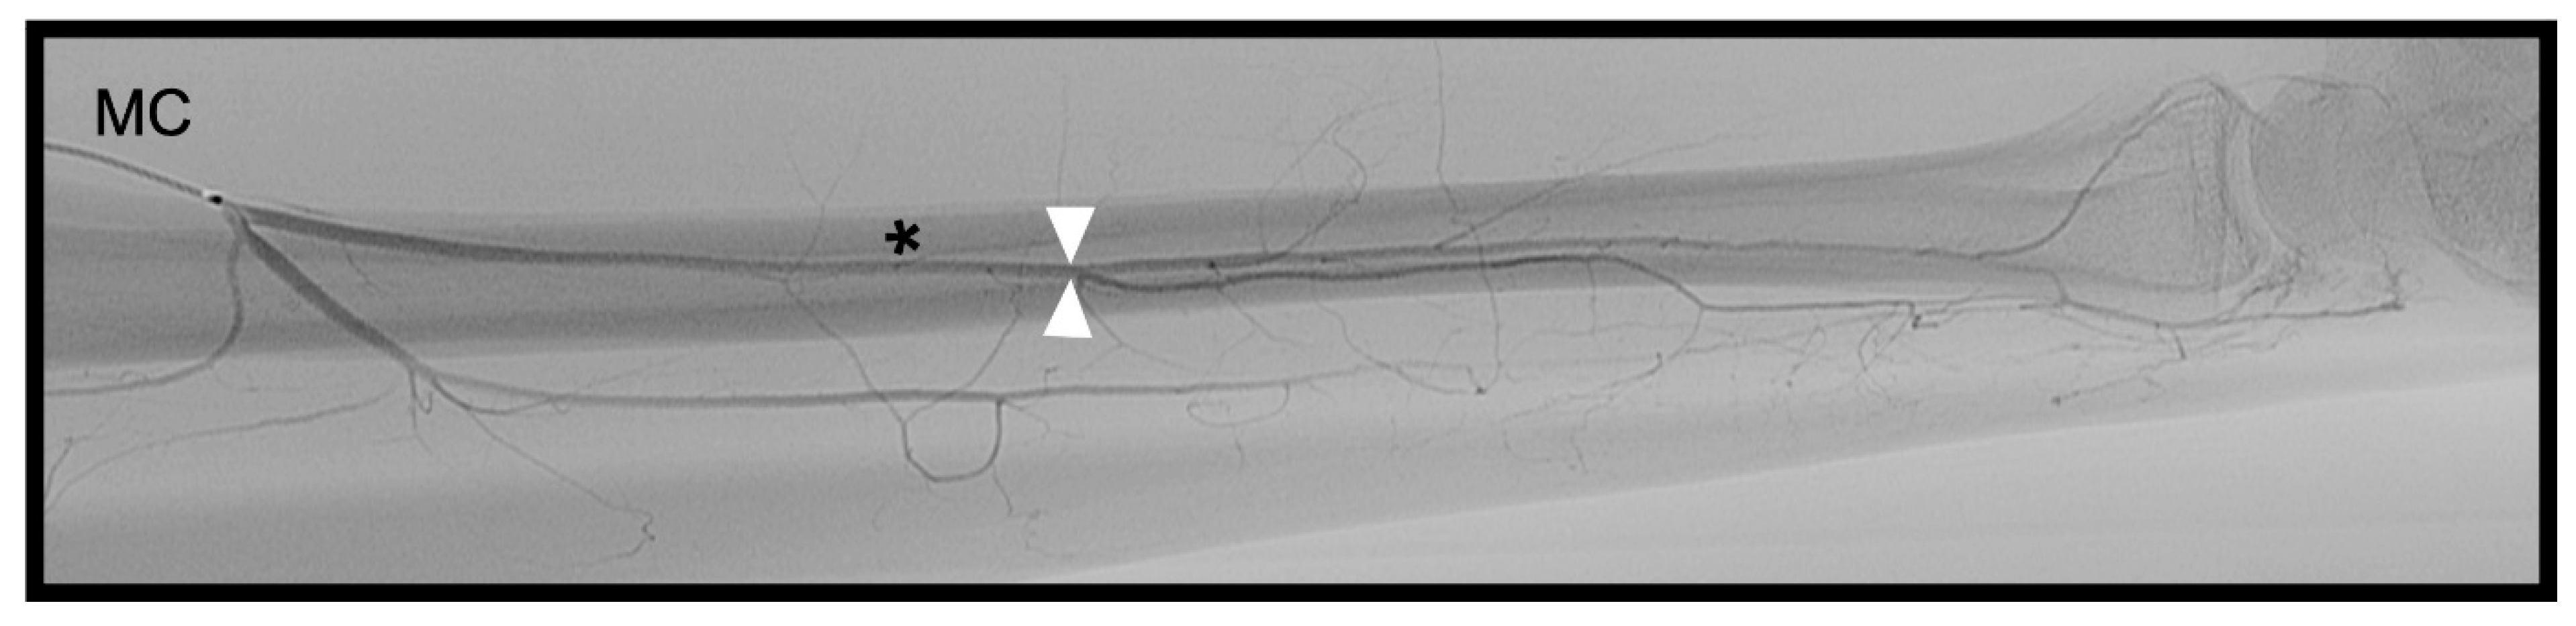

3.2. Dorsal Carpal Branch of the Ulnar Artery (DCBUA)

distance from the DCBUA to the styloid process of the ulnar (DCBUA = dorsal carpal branch of the ulnar artery).